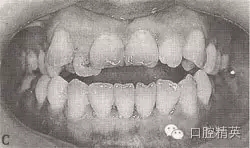

典型病例

患者,女,29歲。恒牙頜,左上6,左下6,右上6,右下6中性。右上321、右下4321,左上123、左下1234開頜5mm。

右上21、右下4321,左上123、左下123反頜。

右上54、右下65,左上4、左下4對頜。

前牙反覆蓋6mm

左上3,右下3唇向。右上54、右下65,左上4、右下4舌向。

左下2外翻,右下6、左下6大面積銀汞充填物,上中線右偏0.5mm,

診斷:安氏Ⅰ類,毛氏Ⅳ2+Ⅱ3+Ⅰ1。

圖9-42 開頜病例矯治前的面頜像

圖9-42 開頜病例矯治后的咬合像

治療:減右上4,右下4,左上6后,直絲弓矯治器+MEAW技術矯治,經2年半治療,擁擠、開頜及反頜畸形得以矯治,咬合關系良好。